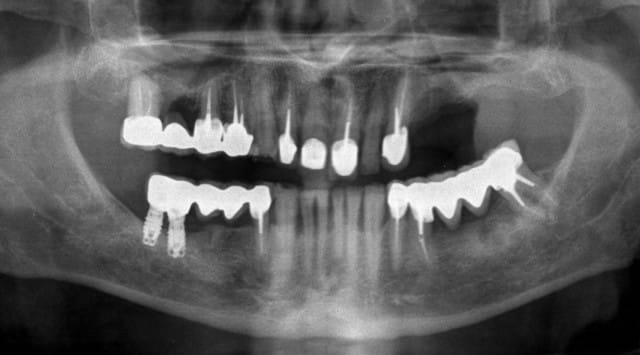

patient adressé pour réhabilitation haut gauche.

devis pour une greffe sinusienne + 4 implants.

le patient voulait absolument un bridge de sa canine à deux implants postérieurs, et sans greffe.

la preuve.

Pourquoi est-ce qu'il ne retourne pas voir celui qui a fait le secteur 4, puisqu'il était si bien ?

il voulait la meme chose qu'en bas donc...

S'il veut la même chose qu'en bas, impossible, il manque un apex oublié en secteur 2 (mais peut-être suis-je abusé par un artefact de ce remarquable cliché que tu n'auras pas pu ou voulu retoucher. ;)

Pourrais tu m'apprendre si la résorption osseuse autour des implants est due seulement à l'hygiène, la tabagie, ou l'option mixte retenue par le confrère?

Je ne suis pas sûr que le patient va trouver de praticien pour faire ce qu'il demande... déjà que le bas droit se fait la malle !!!!